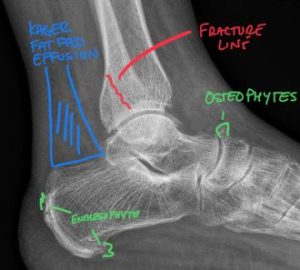

X-rays are a form of radiation that can pass through the body to generate images of internal structures like bones. When these X-rays pass through the body, different tissues absorb them at different levels. For example, denser structures like bone absorb more X-rays and appear white on an image, while softer or less dense structures absorb less energy and appear as shades of gray or black.

In chiropractic care, X-rays are routinely used to visualize the spine and other osseous structures. This helps the chiropractor identify potential problems that might contraindicate chiropractic care and aids in diagnosing the underlying cause of your pain or discomfort. This process guides them in developing a treatment plan for your care.